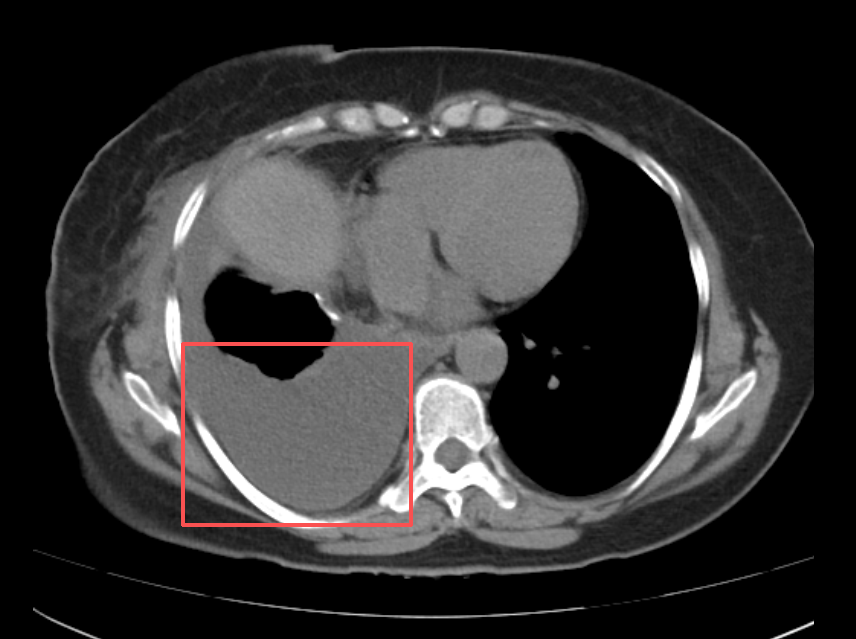

近来,56岁的邹阿姨(化名)活动后反复出现胸闷、气短的症状,到就近医院就诊后,胸部CT检查提示:右侧胸腔内可见约10cm巨大占位,右肺下叶膨胀不全。进一步完善PET-CT检查显示:右侧胸腔背侧占位,FDG代谢不均匀性稍增高,考虑为胸膜来源的低度恶性肿瘤可能大。

术中采用3D单孔胸腔镜技术进行探查。右下肺可见约10cm巨大肿物,明确肿瘤来源后,顺利完成3D单孔胸腔镜下右下肺叶切除术。整个手术在确保肿瘤完整切除的同时,最大程度减少了患者创伤。术后病理结果显示:间叶源性肿瘤,考虑为孤立性纤维肿瘤。